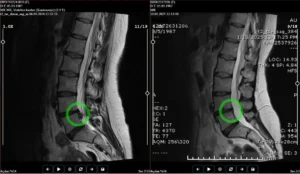

Ameliyatsız Bel Fıtığı Tedavisi

Cerrahi müdahaleye gerek kalmadan bel fıtığına etkili ve güvenli çözümler sunuyoruz